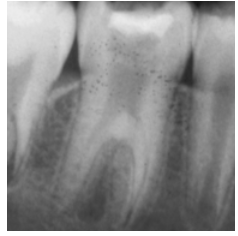

Taurodontism

Vertically elongated pulp chamber & short roots